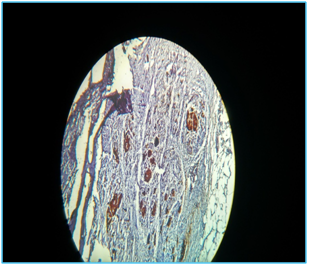

On cut section, the Tumor was capsulated and showed areas of necrosis, hemorrhagic and cystic areas. Microscopically, the tumor composed of oval to round cells arranged in an organoid pattern, separated by a delicate vascular network, giving an appearance of classic Zellballen pattern. The tumor cells have abundant acidophilic cytoplasm containing granules with moderate variation in size and shape and insignificant mitosis. Areas of variable necrosis and hemorrhage were noted (Figure 1) and the diagnosis of pancreatic paraganglioma was made and was advised for IHC. IHC markers includes cytokeratin cocktail which was positive in tumor cells (Figure 2), S 100 positive in sustenticular cells (Figure 3), chromogranin A positive in tumor cells (Figure 4) and invalid presentation of Ki67. The patient’s post-operative course was unremarkable and there was no evidence of recurrence on follow up with USG report.

Figure 1 Variable necrosis and hemorrhage.